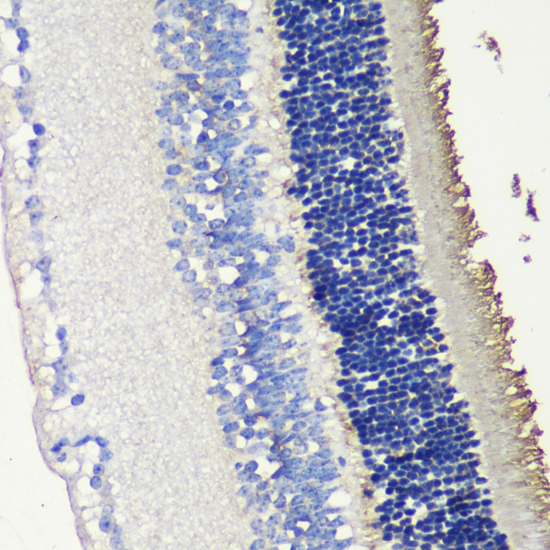

Immunohistochemistry - SAG Polyclonal Antibody

Immunohistochemistry of paraffin-embedded mouse retina using SAG antibody at dilution of 1:200 (40x lens).